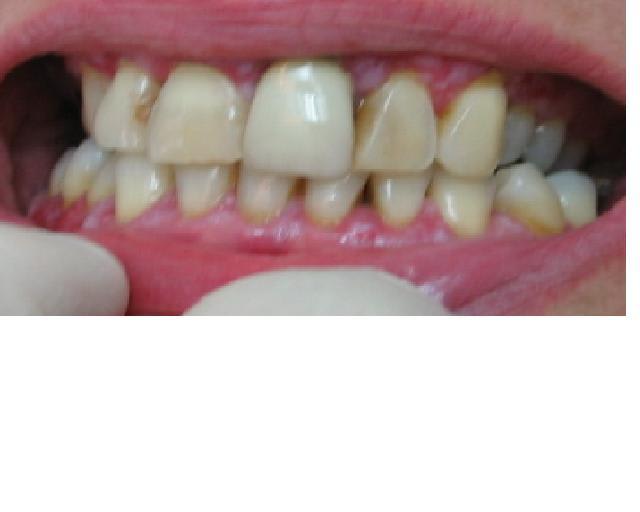

Désolé d'intervenir dans vos vives discussions mais n'y aurait-il pas d'autres étiologies à ces ulcérations?

La patiente fume t'elle? dans ce cas, l'H2O2 est aussi déconseillé.

L'aspect des ulcérations et la couleur de la gencive me font penser à 2 autres étiologies complémentaires au pb hépatique: un brossage traumatique et une hyposialie. La patiente prend t'elle des anti-dépresseurs?

bien à vous,

la patiente ne fume pas, ne prend pas d'antidepresseur et n'as pas la salive caractéristique de l'hyposialie.

je l'envoie chez le stomato avec qui je correspond d'habitude pour confirmer.

réponse bientôt.

une descriptif du lichen plan (merci phil pour le site).